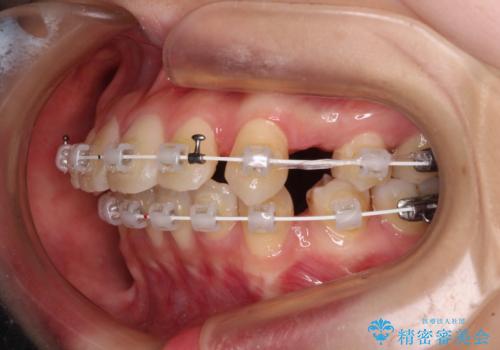

【モニター】口が閉じにくい 抜歯矯正で口元を引っ込める

- 前歯のデコボコや口元の突出感、口の閉じにくさを気にして来院された患者様です。

上下左右第一小臼歯4本を抜歯し、ワイヤー装置にてデコボコを解消しながら口元を引っ込めるよう矯正治療を行うこととしました。

抜歯スペースを閉じている過程で、左側の上下犬歯が引っかかってしまい、進捗が停滞しましたが、当初予定の2年~2年半の間で無事に治療を終えることができました。